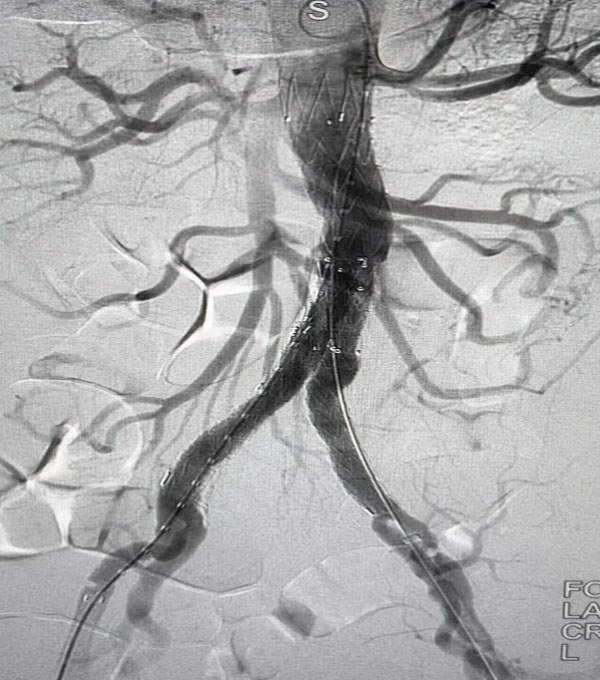

同期,另一臺“升主動脈置換+全主動脈弓置換+胸主動脈覆膜支架腔內隔絕術”正在開展,該病例為一名A型主動脈夾層患者。在主動脈弓及分支成功游離且心臟停跳后,心外科負責人趙永波“轉場”為患者完成了血管置換,心臟復跳成功,止血徹底。隨后,談凌凌主治醫師、侯五輝主治醫師為患者進行胸主動脈腔內修復。下午2點左右,兩臺手術成功結束。通過現場視頻直播,在手術同時,手術人員與大會現場的專家們就影像評估、手術策略、手術器械的選擇及操作技巧等多個環節進行了互動討論,學術氣氛熱烈,大會主席及與會代表給予我院高度評價。緊接著,手術團隊又為一名79歲腹主動脈瘤患者進行了腹主動脈腔內修復手術,效果良好,同樣受到與會專家的好評。

腹主動脈腔內隔絕